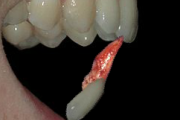

Põhimõtted – Trauma tagajärjel irdunud jäävhammast tasub alati tagasi istutada, kui õnnetuses on hammas ja alveool terveks jäänud. Kui ka hammas hiljem kaotataks, on istutamine tähtis, sest see kergendab implanteerimist ja lükkab edasi hamba asendamist proteesiga. – Mingil juhul ei Loe edasi »